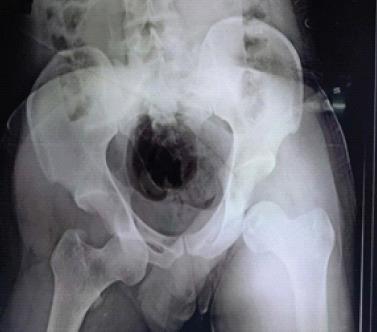

A 26-year-old man was brought to the emergency department following high-energy trauma due to a motor vehicular accident. He was in considerable pain with both hips in flexion, abduction, and external rotation. There was a restriction to the range of movement at bilateral hip joints. Clinical and radiological examination revealed bilateral anterior hip dislocation.

一名26岁男性因机动车事故遭受高能创伤后被送至急诊科。他双髋处于屈曲、外展和外旋位,疼痛剧烈。双侧髋关节活动范围受限。临床及影像学检查显示双侧髋关节前脱位。